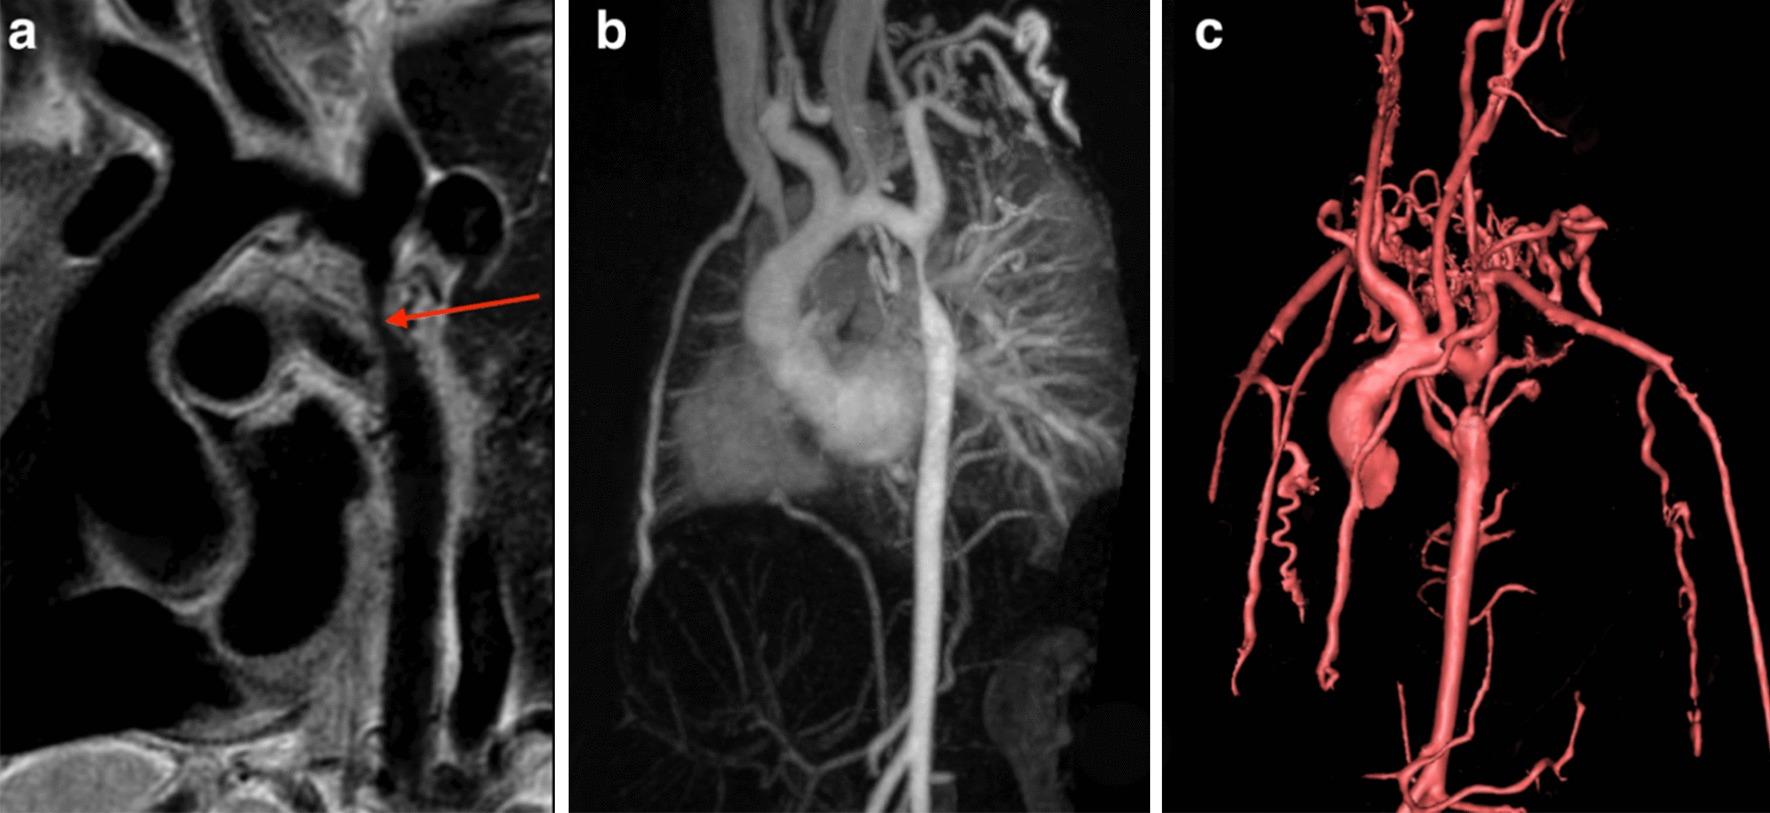

SCMR 立场文件(2020 年):心血管磁共振的临床适应证。

SCMR Position Paper (2020) on clinical indications for cardiovascular magnetic resonance.

The Society for Cardiovascular Magnetic Resonance (SCMR) last published its comprehensive expert panel report of clinical indications for CMR in 2004. This new Consensus Panel report brings those indications up to date for 2020 and includes the very substantial increase in scanning techniques, clinical applicability and adoption of CMR worldwide. We have used a nearly identical grading system for indications as in 2004 to ensure comparability with the previous report but have added the presence of randomized controlled trials as evidence for level 1 indications. In addition to the text, tables of the consensus indication levels are included for rapid assimilation and illustrative figures of some key techniques are provided.

心血管磁共振学会(SCMR)最后一次发布其关于心血管磁共振临床适应证的综合专家小组报告是在 2004 年。本共识小组报告将这些适应证更新到 2020 年,并包括全球范围内扫描技术、临床适用性和采用心血管磁共振的大幅增加。我们使用了与 2004 年几乎相同的适应证分级系统,以确保与之前的报告具有可比性,但增加了随机对照试验作为 1 级适应证的证据。除了文本外,还包括了共识适应证水平的表格,以便快速吸收,并且提供了一些关键技术的说明性图片。